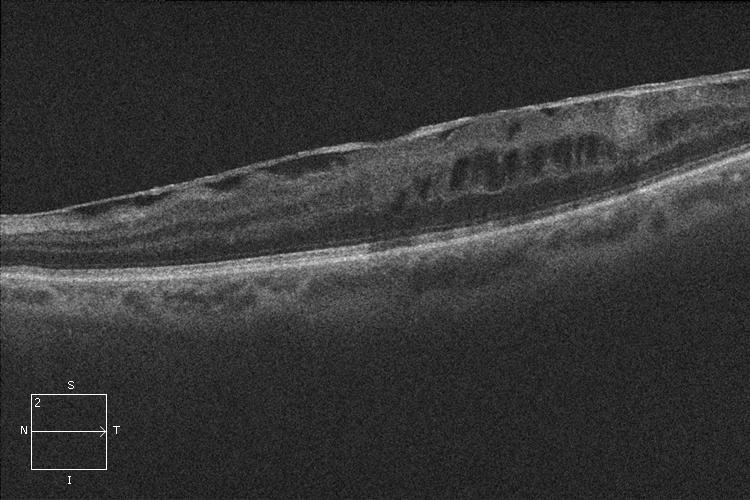

OCT. Membrana epirretiniana

OCT. Membrana epirretiniana antes de la cirugía